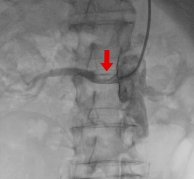

腎動脈ステント留置術

2次性腔血圧の原因として頻度の高い腎動脈狭窄の治療です。腎動脈の狭窄部分に細い針金を通して、風船(バルーン)で病変を開大させます。最近ではステントという金属の支持器具を留置することが多くなっています。血管内超音波という器材で病変の長さや血管径を測定し、病変の正常を確認しながら治療していきます。

突然の血圧上昇や腎機能の悪化などがきっかけで発見されることがあります。

多くの降圧薬でも血圧が下がらない、原因不明の肺水腫などに治療の適応があります。すべての方に腎動脈ステントの適応があるわけではありません。

治療前

治療中

治療後